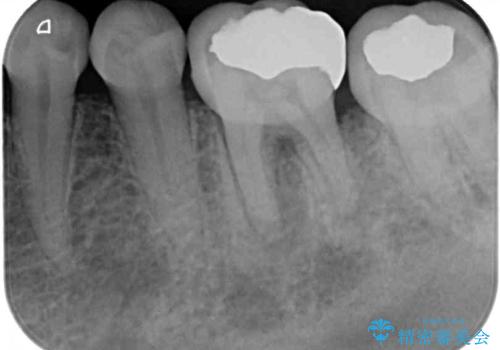

- 左下奥に、咬んだときの痛みを感じて来院された患者様です。

排膿路が形成されている歯は既に失活しており、根管治療が必要になっていました。

根管治療などを行った後に、オールセラミッククラウンにて補綴することとしました。